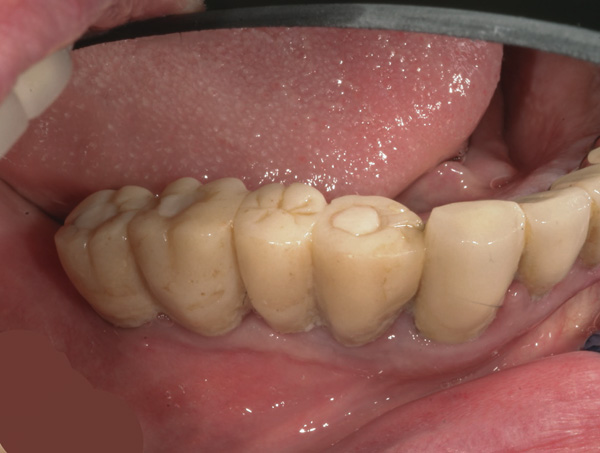

Background: This patient presented with a failing maxillary bridge spanning teeth Nos. 6 through 11. In order to keep the patient in a fixed transitional prosthesis, the first phase of treatment involved placing a provisional restoration on Nos. 6 through 11, with the first set of implants placed at sites Nos. 6 and 11. Once implants Nos. 6 and 11 integrated, custom abutments were placed, and the provisional was relined to add their support. Then implants and their respective subsequent abutments could be placed at positions Nos. 7 and 9 (Figure 20). Tooth No. 8 received elective endodontic treatment in order to be reduced and eventually submerged following insertion of the abutments at Nos. 7 and 9 (Figure 21 and Figure 22).

Results: In Figure 22, it is apparent that there is no recession around abutments Nos. 7 and 9 following root submergence. Of additional note, Figure 23 illustrates excellent bone labial to all the implants, with no recession around abutments Nos. 6 or 11. These first abutments were inserted 8 months prior to the ones at Nos. 7 and 9. The time between Figure 21, when root submergence took place, and Figure 23, when the final bridge was to be inserted, was 7 months. Figure 24 shows placement of the provisional bridge on all abutments.

Figure 20 Implants and their respective subsequent abutments placed at Nos. 7 and 9.

Figure 20

Figure 21 Endodontically treated tooth No. 8.

Figure 21

Figure 22 Tooth No. 8 eventually submerged following abutment insertion at Nos. 7 and 9.

Figure 22

Figure 23 Excellent bone labial to all the implants; no recession around abutments Nos. 6 or 11.

Figure 23

Figure 24 Provisional bridge on all abutments.

Figure 24